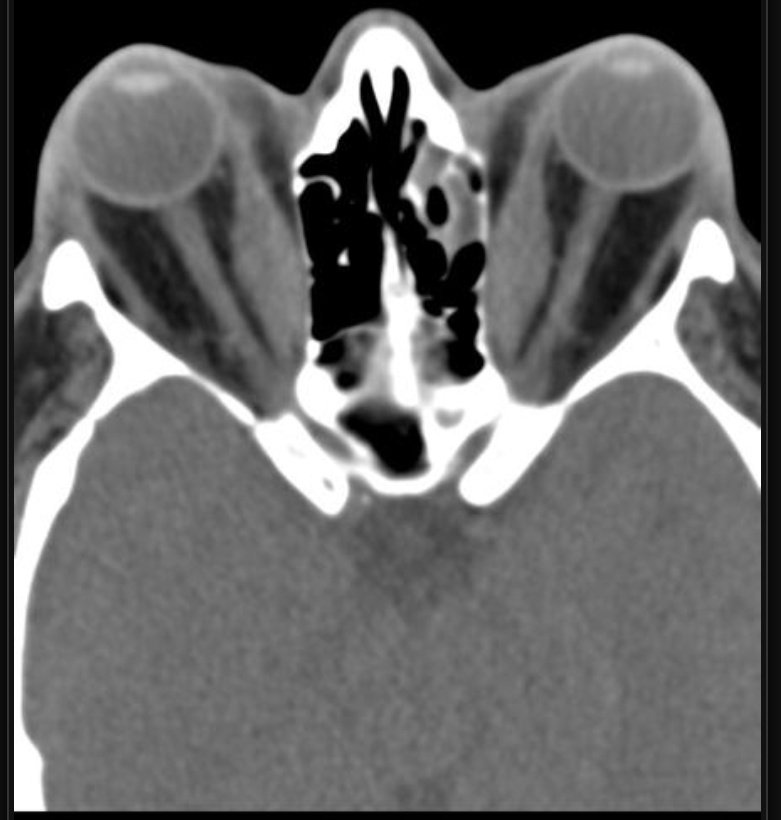

لطالما ربط الإشعاعي المناظر الإشعاعية بأشياء من الواقع ليسهل التعرف عليها أو تذكرها

في هذه الصورة استذكر ابيات عمر بن أبي ربيعة:

قالت الكبرى أتعرفن الفتى

قالت الوسطى نعم هذا عمر

قالت الصغرى وقد تيمتها

قد عرفناه وهل يخفى القمر